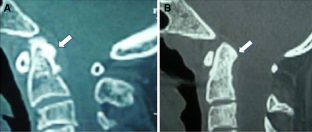

Sixteen adult patients with Chiari I malformation with significant ventral cervicomedullary compression, in the absence of BI, were included in the study. Atlantoaxial dislocation (AAD) was excluded in these patients by flexion-extension craniovertebral junction X-rays and computed tomography (CT). Their clinical profile, especially symptoms pertaining to cervicomedullary compression, i.e. dysphagia, dysarthria and spasticity, were graded. The ventral cervicomedullary compression (VCMC) was quantified using pBC2 (maximum perpendicular distance to the basion-infero posterior point of the C2 body) on sagittal magnetic resonance imaging (MRI) and only those patients with pBC2 ≥9 mm were included. Furthermore, retroversion of dens and retro odonotid tissue thickness was calculated in each patient. Fifteen patients underwent posterior decompression alone and one refused surgery. Follow-up was done every 3 months. Repeat MRI was done at 1 year following surgery to look for pBC2.

The mean pBC2 was 11 ± 0.2 mm. Retroversion of dens was responsible for VCMC in three patients and periodontoid crown in 13. There was no correlation between the tonsillar descent, age and the pBC2. All patients improved in symptoms of cervicomedullary compression following surgery. One patient worsened 6 months after initial improvement. The pBC2 did not change, as seen on follow-up MRI done in five patients.